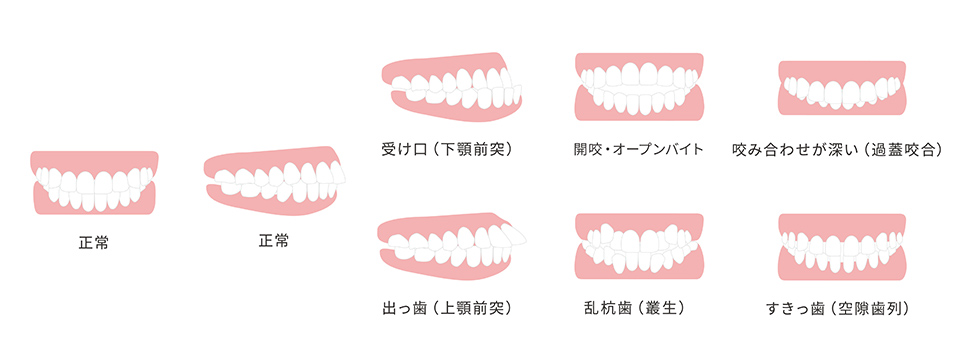

矯正治療とは悪い歯並びや噛み合わせを改善し綺麗な歯並びに整える治療です。

歯並びや噛み合わせを整えることは、お口だけでなく身体全体の健康へと繋がり、顔の筋肉も正しく動かせるようになるため表情も明るくなります。

不正咬合は見た目の悪さだけではなく、お口以外にも様々な問題が生じる場合がありますので歯並びが気になる方は当院までご相談ください。